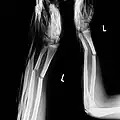

-

Mit ESIN versorgter schultergelenknaher Oberarmbruch beim Kind. Ausheilungsbild mit deutlich sichtbarem Frakturkallus (Pfeil) -

Komplette Unterarmschaft-fraktur beim Kind mit deutlicher Knickbildung -

Versorgung derselben Fraktur mit je einem Prevot-Nagel (ESIN) in Radius und Ulna